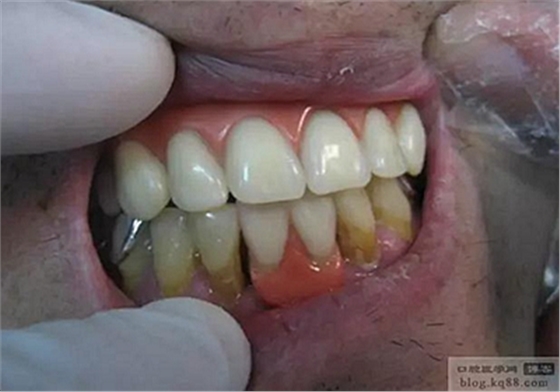

試排牙,外形和笑線都達(dá)到了預(yù)期效果。

調(diào)頜后戴入口內(nèi)的照片,穩(wěn)固程度,美觀程度,豐滿度患者均很滿意。